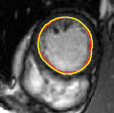

V-D Multiple Region Segmentation: Full Heart Segmentation

We now demonstrate our approach in performing challenging full heart segmentation: segmentation of the ventricles and epicardium all in one shot. Both the RV and epicardium are especially challenging as the contrast of the RV and background is subtle in comparison to the LV, and the myocardium wall near parts of the RV is very thin. We are not aware of another interactive method that is able to segment all structures, and so we compare to Medviso even though the method is not specifically tailored to the myocardium, but the method is generic and is able to propagate a segmentation. Further, Medviso does not segment multiple regions all at once and thus we perform separate segmentation of the LV, RV and epicardium. Since ground truth is not available for the outer wall of the myocardium in any standard dataset that we aware of, we show visual comparison.

Figure 10 shows the slice-wise results of our method and Medviso on a full 3D cardiac MRI sequence for a full cardiac cycle. Results indicate that our method is more accurate in capturing the shape of the ventricles and epicardium, and our method is especially more promising on the RV and epicardium. Figure 11 shows visualization of the results in 3D, and that our method more accurately resembles the structure of the heart.